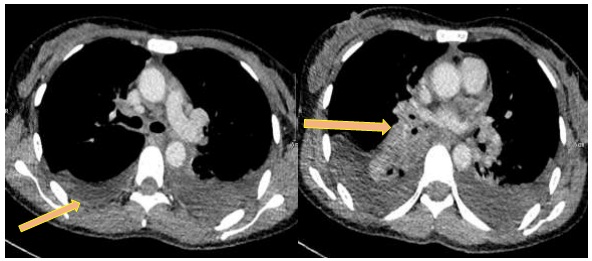

Hình 2: Hình ảnh cắt lớp vi tính ổ bụng: hình ảnh nhiều nốt rải rác nhu mô gan, ngấm thuốc kém, kích thước lớn nhất 29x18mm (vòng tròn vàng).

- Chụp cắt lớp vi tính bụng: Rải rác các nốt nhu mô gan, ngấm thuốc kém, kích thước lớn nhất 12x14mm

So sánh hình ảnh cắt lớp vi tính bụng trước và sau điều trị 3 chu kỳ:

- Chụp cắt lớp vi tính bụng: Nốt giảm tỷ trọng nhu mô gan phải, kích thước 12x14mm, ngấm thuốc kém sau tiêm